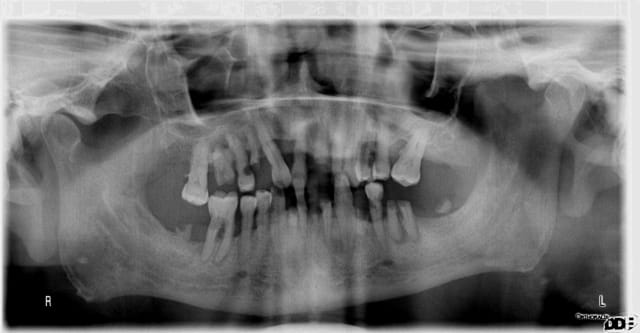

Il a quand même tiqué à la pano...

Puis il a recommencé comme avant.

Le pire est que je ne peux rien faire pour l'aider et c'est quelque chose que je ne peux pas accepter. Nous avons affaire à un individu intelligent, plus que la moyenne, et têtu comme une mule.